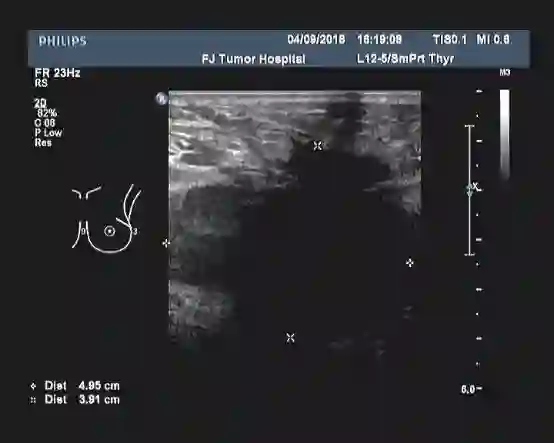

女性患者,30岁,未绝经,家族史不详(患者本人为领养)。于2018-01发现左乳肿块,当地医院乳腺MRI示:左侧乳腺外上象限可见5*7cm大小团块状影,左侧腋下可见多个肿大的淋巴结。B超提示:左乳外上象限探及一低回声区,大小约4.9cm×3.9cm,边缘不规则,可见成角、毛刺,内部回声不均;左腋上中下组探及数个低回声,大者约2.2cm×1.8cm,边界尚清,类圆形,皮髓质分界不清,皮质不规则增厚,淋巴结门消失;右乳及右腋窝未见异常。 PET-CT结果:1、考虑左乳外上象限癌累及胸大、小肌。 2、考虑左锁骨区、左胸大肌及胸小肌深面、左腋窝多发淋巴结转移。

▎初步诊断:左乳浸润性癌(cT3N3M0 IIIc期)